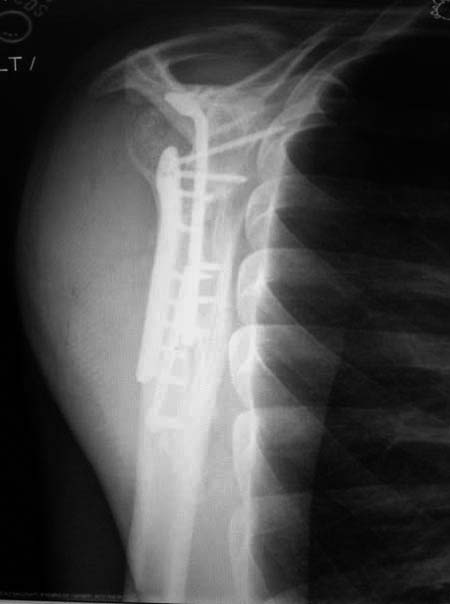

Здесь пример, стандартные снимки: плечо и лопатка прямой снимок, аксиллярный и косой снимки (Y-view) и фиксация пластинами по краям, где имеется более твердая кость. Специальные пластины, хотя любая 2.7 или 3.5 мм тубулярная пластина подойдут для фиксации перелома. Риск операции - это повреждение нерва во время доступа и ре-фиксация ротаторной манжетки если потребуется широкий доступ!